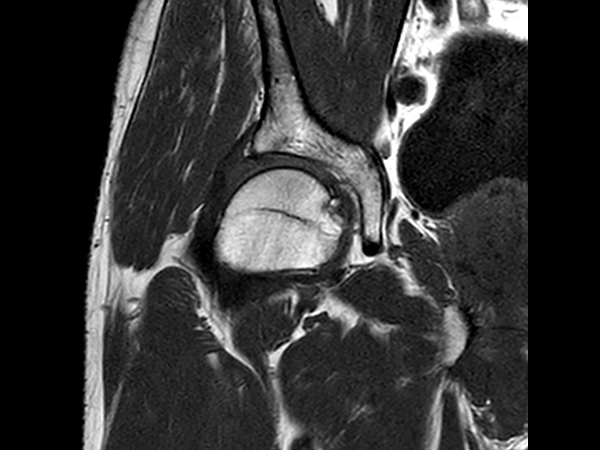

Sagittal T2w TSE

-